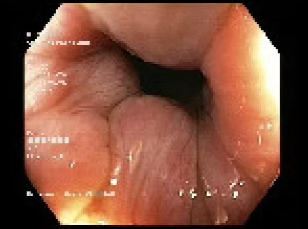

The colonoscopy was inserted to the terminal ileum. An inverted appendix measuring 30mm was visualised in the caecum (Figures 1&2). No obvious lesion was seen on the mucosal surface of the appendix. No signs of small bowel or colonic intussusception was evident. The colonoscopy was otherwise unremarkable, except for some small second degree haemorrhoids (Figure 3) No biopsy was taken. Patient was well post colonoscopy.